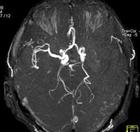

(2)MRI:可清晰显示早期缺血性梗死脑干及小脑梗死静脉窦血栓形成等梗死后数小时即出现T1低信号T2高信号病灶,出血性梗死显示其中混杂T1高信号。钆增强MRI较平扫敏感。功能性MRI弥散加权成像(DWI)可早期诊断缺血性卒中,发病2h内即显示缺血病变为早期治疗提供重要信息。DSA可发现血管狭窄及闭塞部位,显示动脉炎、Moyamoya病、动脉瘤和动静脉畸形等。

2.经颅多普勒(TCD)可发现颈动脉及颈内动脉狭窄、动脉粥样硬化斑或血栓形成。超声心动图检查可发现心脏附壁血栓、心房黏液瘤和二尖瓣脱垂。